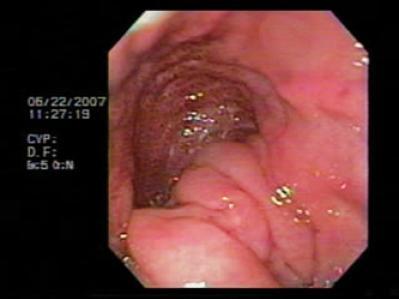

Patient was referred for endoscopy which found an organoaxial gastric volvulus (Figure 8) and a para-esophageal hiatal hernia. Endoscopic devolvulation was decided upon. An alpha shaped loop was initially placed (Figure 9), followed by passage of the endoscope to the antrum. Clockwise rotation of the equipment and consequent devolvulation were then performed (Figure 10). The patient was referred to the outpatient clinic for treatment of his para-esophageal hernia.

Figure 8. Observe how, as in our first case, the gastric folds are on the upper part of the screen with a stenosis in the middle of the stomach. The stenosis obstructs easy passage of the endoscope as well as passage of food.